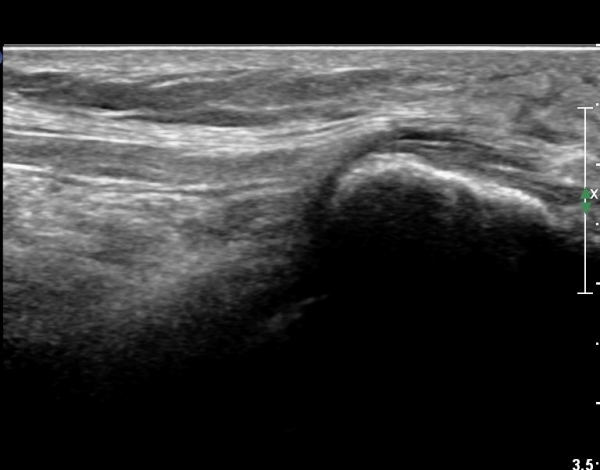

ŽÃËÀÚ¸¦ Á» ´õ ¸»´Ü, ¿ÜÃøÀ¸·Î À̵¿ÇÏ´Ï ºñ°ñµÎ Ç¥Ãþ¿¡¼­ ºñ°ñ½Å°æÀÌ Àú¿¡ÄÚ·Î °üÂûµÈ´Ù(»çÁø 3, 4, 5).